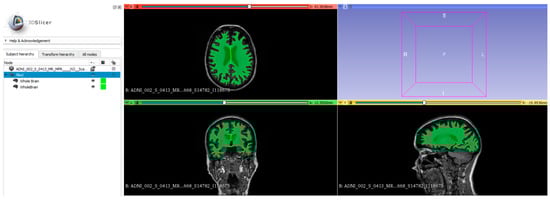

2.2. Brain Segmentation and Regional Volume Analysis